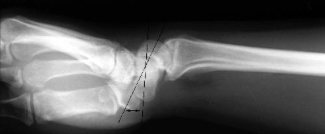

Lateral